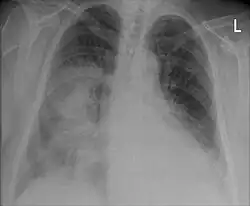

In der Lungenheilkunde (Pneumologie) versteht man unter Konsolidierung eine Ansammlung von Exsudat, Transsudat oder anderem Gewebe in den Lungenbläschen (Alveolen). Dadurch wird die Luft aus den Alveolen verdrängt und die eigentliche Funktion des Gasaustausches kann nicht mehr erfüllt werden. In Röntgen- und Computertomographiebildern der Lunge stellen sich die Konsolidierungen der Alveolen als röntgendichte (helle) Strukturen dar, da sie für die Röntgenstrahlen weniger durchlässig sind als das normale Lungengewebe. Konsolidierungen der Lunge kommen vor allem im Rahmen von Entzündungen und Fibrose vor, z. B. bei Lungenentzündungen und interstitiellen Lungenerkrankungen.